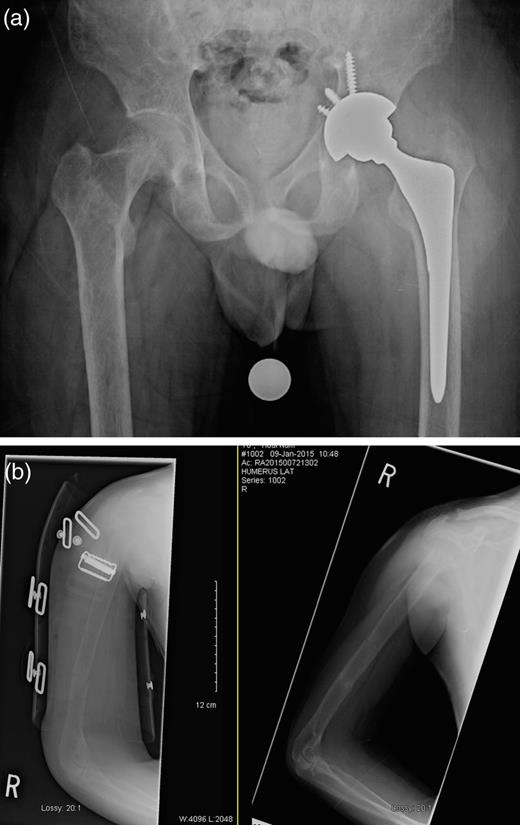

A 22-year-old male student presented to our hospital with a 2-year history of progressive lower extremity weakness. One year prior to the admission, he had been seen at another medical clinic because of fatigue and difficulty walking. His radiographs showed no fractures, and he was referred to physiotherapy for muscle strengthening. He underwent 5 months of physiotherapy. Given the lack of progress, his therapist advised him to be reassessed medically. This time, he presented to the Family Medicine clinic at our hospital. Further questioning revealed that, despite physiotherapy, his weakness had progressed and he had to quit school as he was having considerable difficulty walking up a flight of stairs. A thorough investigation was performed and showed a serum calcium level of 3.46 mmol/l (normal: 2.1–2.6 mmol/l) and a PTH level of 138 pmol/l (normal: 1.6–9.3 pmol/l). A parathyroid scan revealed a parathyroid adenoma. He was referred to our General Surgery service where he was admitted for excision of the parathyroid adenoma. Upon admission, radiographs of his pelvis showed no fracture, but severe osteopenia was observed. One day prior to the scheduled parathyroidectomy, he had a simple, low-energy fall while he was walking on his own to the hospital. Radiographs revealed a displaced subcapital fracture of his left hip, a segmental fracture of his right humerus and extreme osteopenia (Fig. 1).

(a) Left femoral neck displaced subcapital fracture and (b) right humeral shaft segmental fracture.